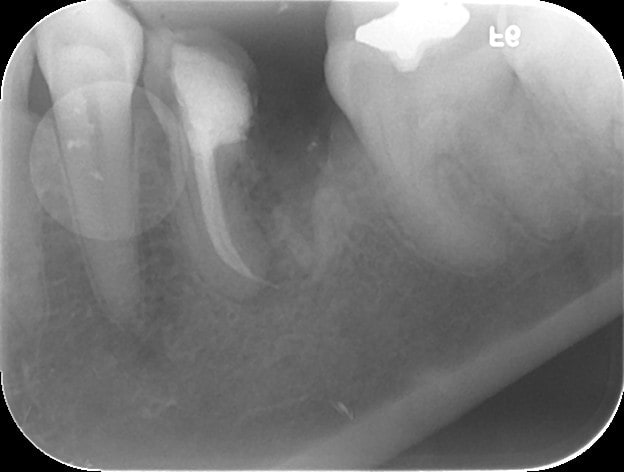

De la à dire que nos propositions thérapeutiques sont influencées par la nomenclature... Je dirais qu'elles sont plutôt influencée par nos aptitudes et/ou nos inaptitudes!

Patiente venue me voir en septembre 2011, après avoir été charcuté par un dentiste qui ne maitrisait visiblement pas la cavité d'accès (lime cassée et perforation monstrueuse)... et s'être vu proposé un implant par deux autres dentistes.

Hemisection 1   20092011 ym6khl - Eugenol

H misection 2   26092011 tzinao - Eugenol

H misection 3   29092011 cpywb0 - Eugenol

H misection 4   12112014 cp4xrk - Eugenol